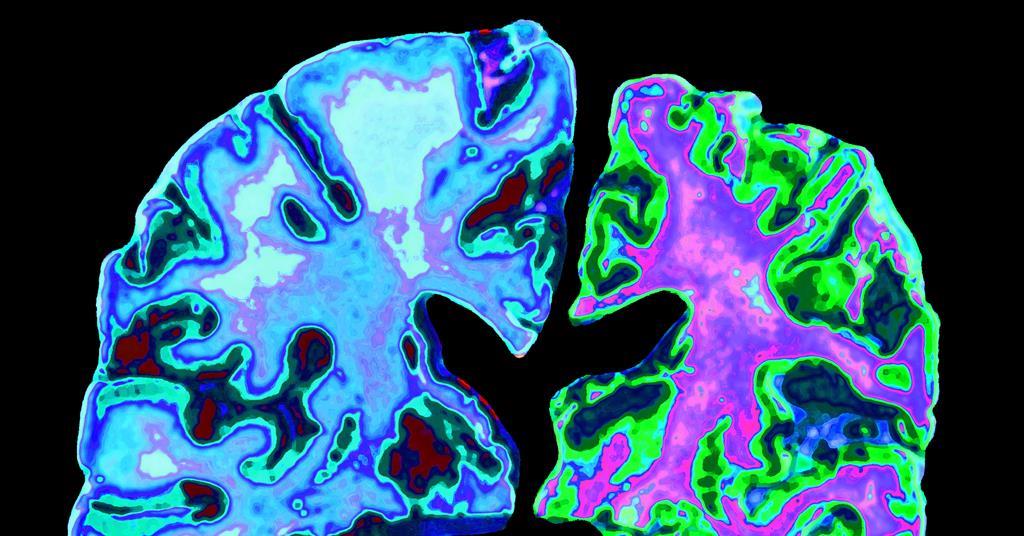

Telltale protein fragment discovered in Alzheimer’s patients could be

Telltale protein fragment discovered in Alzheimer’s patients could be Medicare Did Not Pay For Blood Tests Medicare part b (medical insurance) covers medically necessary clinical diagnostic laboratory tests, when your doctor or provider orders them. Someone with coverage from original medicare will usually have no charge for diagnostic blood tests, but someone with a medicare advantage plan may be. They can help you understand why you need certain tests,. What it is laboratory tests include certain. Medicare Did Not Pay For Blood Tests.